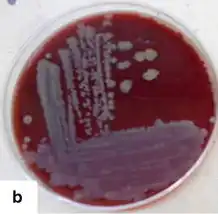

| Gram stain of Corynebacterium xerosis | |

Corynebacterium xerosis is a gram-positive, rod-shaped bacterium in the genus Corynebacterium. Although it is frequently a harmless commensal organism living on the skin and in the mucous membranes, C. xerosis is also a clinically relevant opportunistic pathogen that has been attributed to many different infections in animals and humans.[1][2] However, its actual prominence in human medicine is up for debate due to early difficulties distinguishing it from other Corynebacterium species in clinical isolates.

Despite normally being a commensal organism, C. xerosis has been linked to many different opportunistic infections in humans and animals, including endocarditis, sepsis, abscesses, and osteomyelitis.[8][9][10][11][12] However, it is possible that many early reports of this bacterium may have been cases of misidentification: a 1996 study found that out of 25 clinical isolates originally identified as C. xerosis, all were actually Corynebacterium amycolatum based on a number of biochemical tests which came back as different from the C. xerosis reference strain.[13] Similarly, there is also evidence that some infections attributed to C. xerosis may have been caused by Corynebacterium striatum.[14] Therefore, it is difficult to determine the actual extent of C. xerosis infections as reported in historic literature; however, modern sequencing and phenotypic analyses have allowed for more accurate identification of C. xerosis in clinical infections.[15]